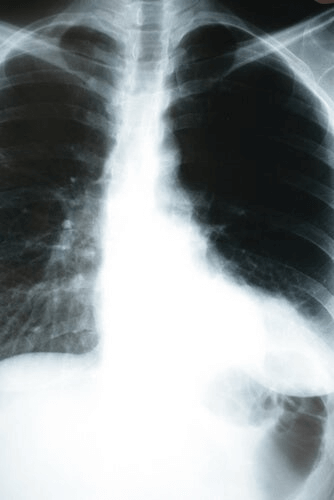

La pneumonie est une infection qui touche les alvéoles du poumon. Il s’agit de petits sacs recouverts de vaisseaux sanguins dans lesquels se produisent des échanges gazeux, c’est-à-dire que le dioxyde de carbone (CO2) est expulsé et que l’oxygène est absorbé de l’extérieur. C’est pourquoi les conséquences de la pneumonie sur l’organisme sont si importantes.

On estime qu’il y a 2 à 10 cas pour 1000 habitants par an, dont 20 à 35 % nécessitent une hospitalisation. Chez les patients ne souffrant pas d’autres maladies, la mortalité est de 1 %, mais peut atteindre 40 % chez les patients admis, notamment dans les unités de soins intensifs (USI). Selon la situation du patient, cela peut être grave.